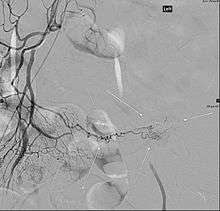

Patients with these misplaced gastric cells may experience peptic ulcers as a consequence. Therefore, other tests such as colonoscopy and screenings for bleeding disorders should be performed, and angiography can assist in determining the location and severity of bleeding. Colonoscopy might be helpful to rule out other sources of bleeding but it is not used as an identification tool.

Angiography might identify brisk bleeding in patients with Meckel's diverticulum.[5]